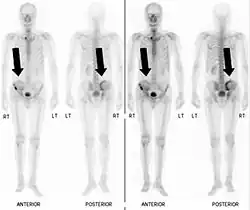

Bone scintigraphy

Also known as a bone scan, bone scintigraphy involves the injection of a small amount of radioactive tracer into the bloodstream. This tracer decays and emits radioactive energy which can be detected by a special camera. The camera produces a black and white image where areas shown as dark black indicate bone damage of some kind. If there is a black spot in the lumbar vertebrae (e.g. L5) this indicates damage and potentially spondylolysis. If this test is positive, a CT scan is usually ordered to confirm spondylolysis.[15]

Commonly known as a CT Scan or CAT scan, this form of imaging is very similar to x-ray technology but produces many more images than an x-ray does. The multiple images produce cross-sectional views not possible with an x-ray. This allows a physician or radiologist to examine the images from many more angles than an x-ray allows. For this reason the CT scan is much more accurate in detecting spondylolysis than an x-ray. Bone scintigraphy combined with CT scan is considered the gold standard which means that it is best at detecting spondylolysis.[15][17]